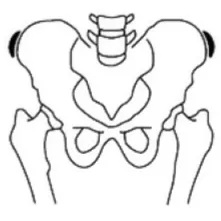

골반 엑스레이 검사 (risser sign) 검사로 성장 정도 파악

Risser 0

Risser 1

Risser 2

Risser 3

Risser 4

Risser 5